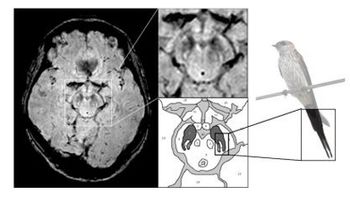

Emerging technology gives radiologists an unprecedented view of the brain.